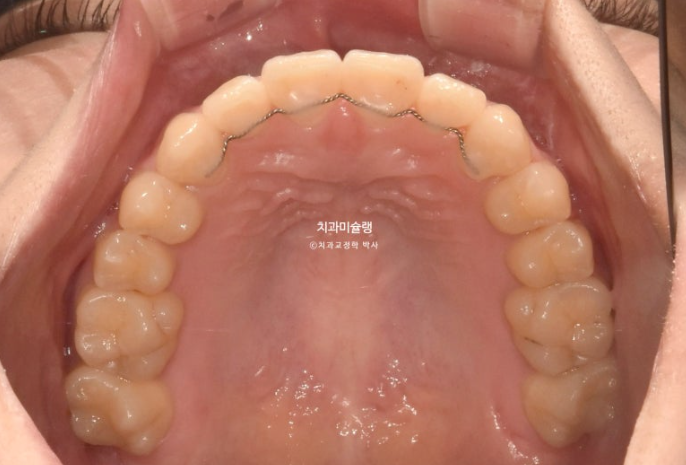

23.09~25.07

아랫니가 뒤로 들어가면서 앞니가 거꾸로 물리는 상태 즉 반대교합은 해소되었습니다.

23.09~25.7

위 앞니에 초진시 이전 교정에 의한 치근흡수가 꽤 있는 상태였는데

이번 1년 10개월의 재교정 치료 기간동안 더 심해지지는 않았습니다.

치근 평행도는 좋습니다.